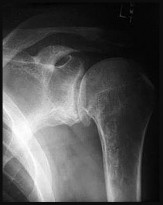

Question 1:

A 12-year-old obese male presents with left groin pain and an altered gait. Based on the presumed diagnosis of slipped capital femoral epiphysis (SCFE) shown in the representative radiograph, which of the following is the primary blood supply to the femoral head that is at highest risk for iatrogenic injury during percutaneous in situ pinning if the pin is placed in the posterosuperior quadrant?

The primary blood supply to the capital femoral epiphysis in children over the age of 3 is the posterosuperior retinacular vessels (lateral epiphyseal artery), which are terminal branches of the medial circumflex femoral artery (MCFA). During in situ pinning for SCFE, placement of the pin in the posterosuperior quadrant of the femoral neck/head places these extracapsular vessels at extreme risk of injury, potentially leading to avascular necrosis (AVN). Pins should ideally be placed in the center-center position to minimize this risk.